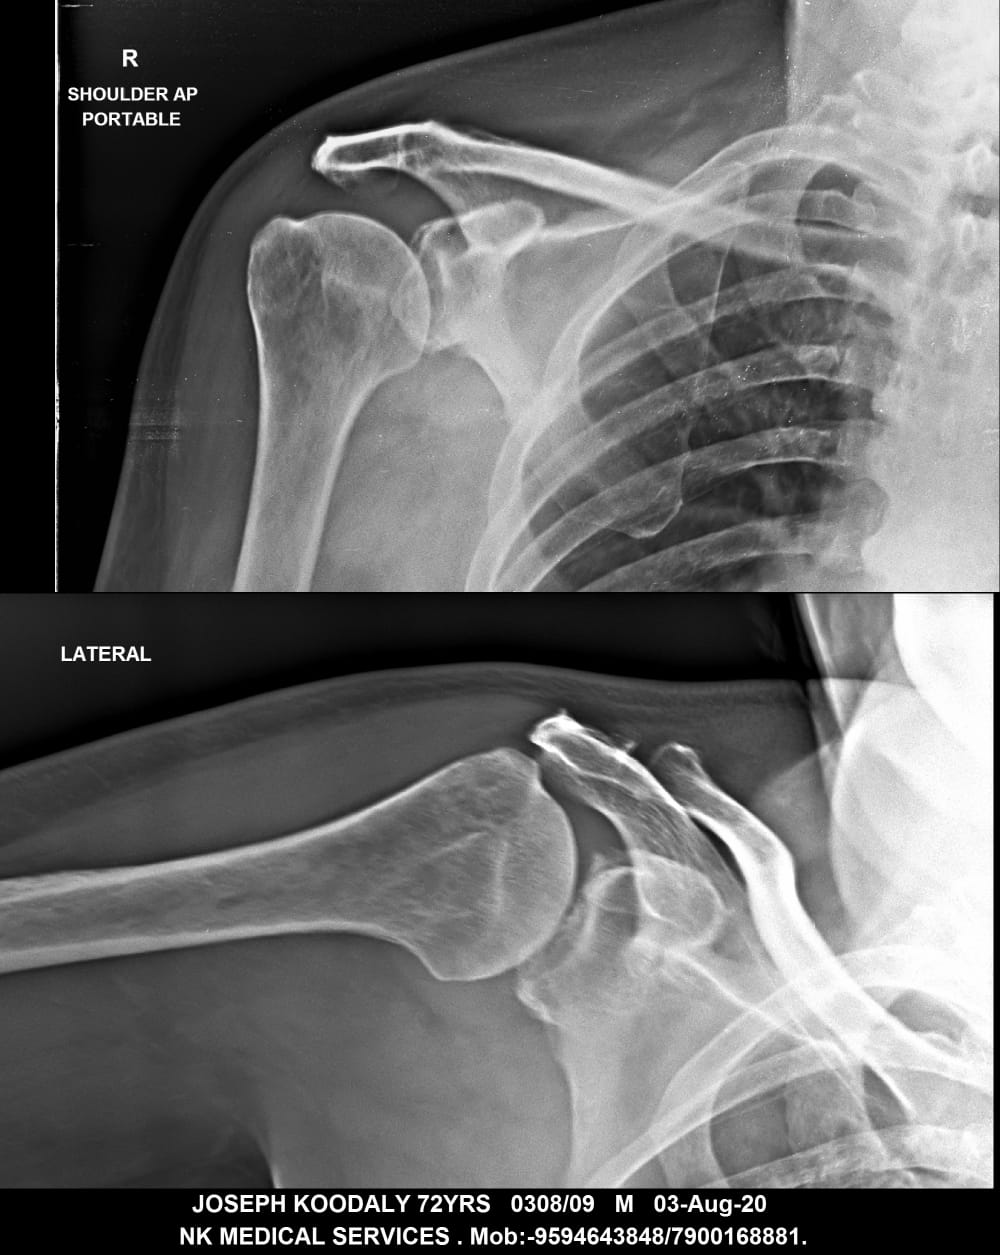

Getwell Urgent Care of Southaven uses digital X-ray technology, which uses less radiation, provides fast turnaround of images, and gives us the ability to manipulate images for more accurate readings. We follow the highest safety standards, with certified equipment and licensed radiology technologists to ensure an excellent image the first time and minimal exposure to radiation. We use digital X-ray to diagnose broken bones, certain lung conditions (e.g., pneumonia), and certain abdominal conditions.